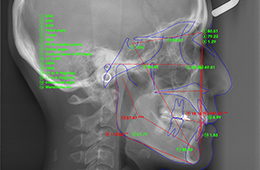

正確な診断を行うには、正しい検査結果が必要です。そしてそのために、きちんと検査を行います。視診、プロービング検査、レントゲン撮影、CT検査などを症状に応じて必要な検査を行います。

これによって、むし歯の状態、かぶせ物の適合具合やお口の衛生状態、歯周病の進行具合、親知らず・顎の骨の状態など様々なことが分かります。また、検査資料を使いますので、説明がより可視的で分かりやすくなっています。